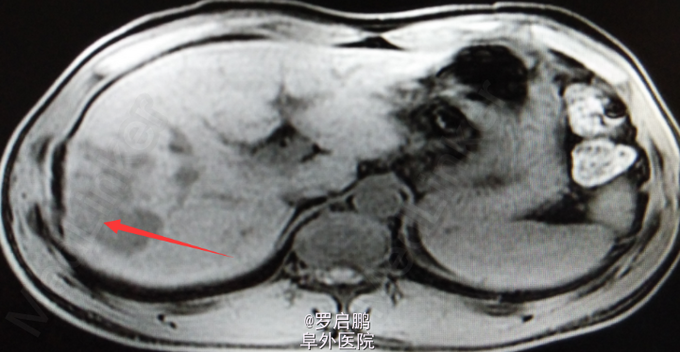

患者 男 48岁 主诉:发现肝脏占位半月 现病史:半月前患者因慢性乙型肝炎复查腹部超声发现右肝占位 既往:慢性乙肝20年,未规律治疗。 个人史:吸烟史25年20支/天,饮酒史13年,白酒2两/次。

超声:右肝高回声光团,胆囊、肝内外胆管、脾脏、双肾未见异常 腹部MRI:肝右叶占位 腹部平扫+增强:肝右叶占位,肝内多发小密度,左肾囊肿,腹膜后淋巴结肿大

肝右叶占位,肝癌? 前入路右半肝切除,LC 鉴别诊断:原发性肝癌;肝转移癌;肝海绵状血管瘤;肝腺瘤;血管平滑肌脂肪瘤。

注意术中循环维持,备血、血浆。术中平稳。术中病理:(右半肝)低分化胆管腺癌,可见坏死,肝内可见多发卫星灶,紧邻肝被膜,切缘未见特殊。术后恢复良好出院。